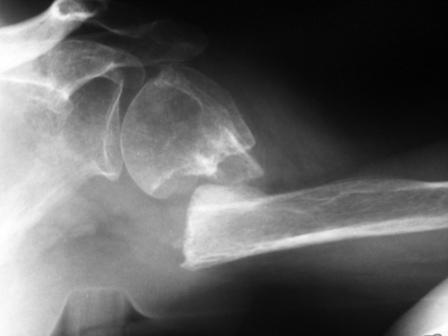

Уважаемые коллеги! Госпитализирована больная 51года. Травма - перелом

хирургической шейки плеча в феврале 2009г. Лечилась по месту

жительства Лонгетной гипсовой повязкой. На фоне сформировавшегося

ложного сустава работает маляром. Объем движений и сила естественно

ограничены. При обсуждении тактики лечения возникли разногласия по поводу вида остеосинтеза и его

целесообразности.